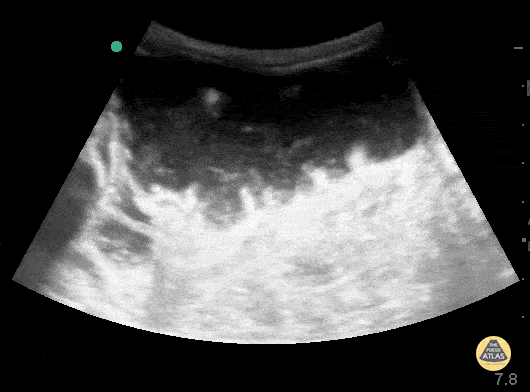

60 y/o M hx CHF, ventral hernia s/p repair p/w abdominal pain, nausea, vomiting without flatus. POCUS shows dilated fluid filled small bowel loops > 3 cm in size. There are signs of bowel wall edema with folds projecting into the lumen known as "piano sign" as well as alternating propulsive and retrograde movement of contents which is frequently described as "washing machine sign" typically seen in small bowel obstruction. Jaramillo, Juliana MD; Shah, Rushabh MD; Aherne, Andrew MD; Cutright, Molly MD.